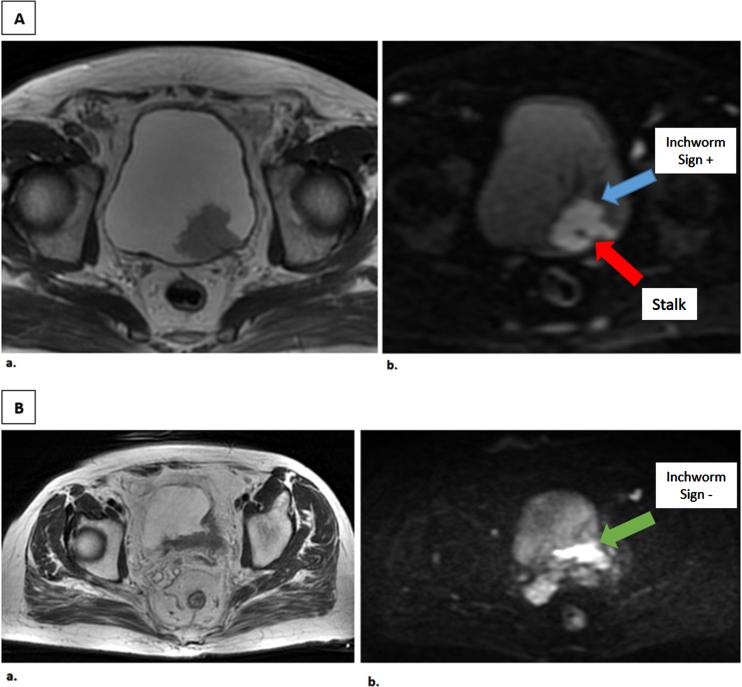

Inchworm sign is a finding on diffusion-weighted magnetic resonance imaging (DWI-MRI) and is used to better stratify T-staging in muscle invasive (MIBC) and non-muscle-invasive bladder cancer (NMIBC). An uninterrupted low submucosal signal on DWI, defined as inchworm sign (IS), indicates NMIBC.

尺蠖征是弥散加权磁共振成像(DWI-MRI)上的一种表现,用于更好地对肌层浸润性膀胱癌(MIBC)和非肌层浸润性膀胱癌(NMIBC)进行T分期。DWI上连续的低黏膜下信号,定义为尺蠖征(IS),提示NMIBC。